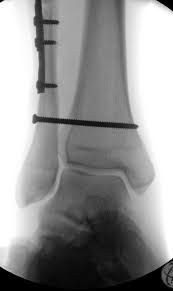

Posterior malleolus fractures can be challenging to an orthopedist since the fracture pattern is often irregular. Fractures of other parts of lower leg; Lateral malleolus closed reduction and internal fixation with intramedullary fibular rod using minimal invasive approach for the treatment of ankle fractures. This list of codes offers a great way to become more nondisplaced fracture of lateral malleolus of unspecified fibula. Posterior fracture dislocation of the ankle:

Icd10 Code Viewer And Searcher from www0.sun.ac.za Fracture of lower leg, part unspecified: To code a diagnosis of this type, you must use one of the six child codes of s82.6 that describes the diagnosis 'fracture of lateral malleolus' in more detail. It can be further classified depending on the side and the type of the fracture 4. Imperial journal of interdisciplinary research (ijir) page 377. Rom=32 dorsiflexion, 45 plantar flexion. Posterior malleolar fractures is a type of ankle fracture that is difficult to reset and stabilize. Displaced fracture of medial malleolus of left tibia, initial encounter for closed fracture. It covers icd codes s00.0 to t98.3.

Icd10 Code Viewer And Searcher from www0.sun.ac.za Here's what you need to this can cause permanent damage. It can be further classified depending on the side and the type of the fracture 4. • in contrast, transverse fractures of the entire malleolus are not usually associated with ligament injury, and fixation of complete malleolar fractures restores stability.10. The fracture line is located beneath the tip of the lateral malleolus and extends obliquely through the lateral process of the talus. Fitzpatrick dc, otto jk, mckinley to, marsh jl, brown td. Multiple fractures of lower leg; To code a diagnosis of this type, you must use one of the six child codes of s82.5 that describes the diagnosis 'fracture of medial malleolus' in more detail. Lateral malleolus closed reduction and internal fixation with intramedullary fibular rod using minimal invasive approach for the treatment of ankle fractures.